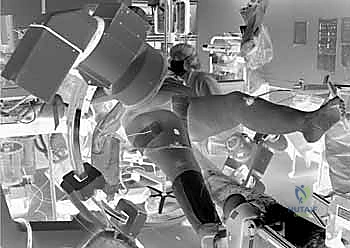

يبدأ الإجراء باختيار نوع التخدير المناسب (غالباً تخدير نصفي شوكي أو تخدير عام) بناءً على تقييم طبيب التخدير. يُنقل المريض إلى طاولة عمليات خاصة تُسمى (طاولة الكسور - Fracture Table). هذه الطاولة تسمح بشد الساق المصابة وتدويرها لرد الكسر (إعادته لوضعه الطبيعي) دون الحاجة لفتح جراحي كبير.

2. الرد المغلق (Closed Reduction)

باستخدام جهاز الأشعة السينية المرئية المستمرة (C-Arm Fluoroscopy) داخل غرفة العمليات، يقوم الدكتور هطيف بإعادة العظام المكسورة إلى محاذاتها التشريحية الصحيحة عن طريق الشد والتدوير الخارجي للساق، وكل ذلك يتم مراقبته على الشاشة بدقة متناهية.